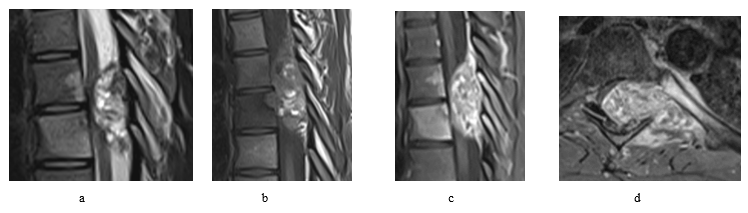

The patient was 19-year-old at time of presentation in early January/2023. He was presented to our spine unit with an incidental finding of T7 lytic lesion with extensive soft tissue involvement (Figure 1 and 2) as seen on CT first, followed by MRI scans. The CT images had been performed as a follow up scans for a previous spontaneous pneumothorax that has been treated for its recurrence with video-assisted thoracoscopic surgery (VATS) combined with left upper lobe apical wedge resection (a bleb inside) and talc pleurodesis in early June/2022. Back then, the x-rays and CT scans for the chest didn’t show a convincing mass lesion (some early lytic changes have been noticed in advance at left T7 pedicle thought to be benign). At presentation, patient had reported 2-week history of back pain and altered sensation from abdomen below with unsteadiness on feet. On exam, patient found to have normal power on limbs, reduced sensation from T7 below and hyperreflexia of knee and ankle. Otherwise, examination was normal. PET scan didn’t show any metastatic lesions.

Figure 2: Pre op spinal MRI shows aggressive osseous lesion centred at the left T7 pedicle with large soft tissue component. The extra-dural soft tissue extension results in complete effacement and compression of the thoracic cord at the T6-T7 level. Given the aggressive appearance and multiple vertebral level involvement, this is favoured to represent an osteosarcoma but an aggressive osteoblastoma remains a differential as does an aneurysmal bone cyst (though this is felt less likely)